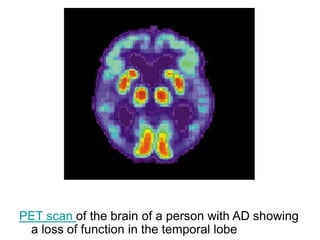

PET scan of the brain of a person with AD showing

a loss of function in the temporal lobe

PET scan ofthe brain of a person with AD showing a loss of function in the temporal lobe